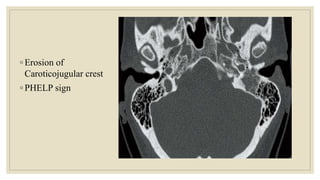

ROSE CASE GLOMUS TUMOR SRS | PPT

ROSE CASE GLOMUS JUGULARE | PDF